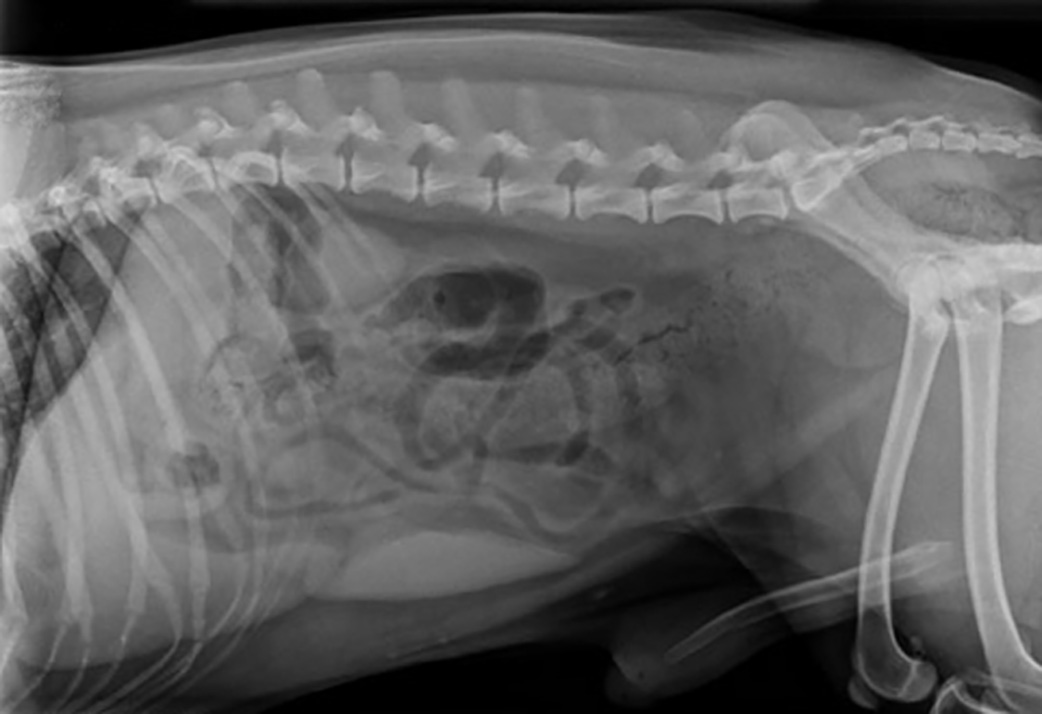

Sylacauga Veterinary Hospital uses digital radiography to examine interior organs and assess the status of injuries or diseases that may be present. With digital radiography, we can check your pet’s internal structures such as bones to diagnose fractures or arthritis, determine the size and location of tumors or foreign objects, discover pregnancies, bladder stones, chronic arthritis, and more. Digital radiography provides clear, precise images quickly, safely, and with less stress for your pet.

Across the board, digital radiography enables Sylacauga Veterinary Hospital to provide better animal care because it gives us the tools to make more accurate diagnoses and develop treatment plans quickly and efficiently. Our practice is convenient to pets in Sylacauga, Oak Grove, Talladega, Alexander City, Childersburg, and everywhere in between.